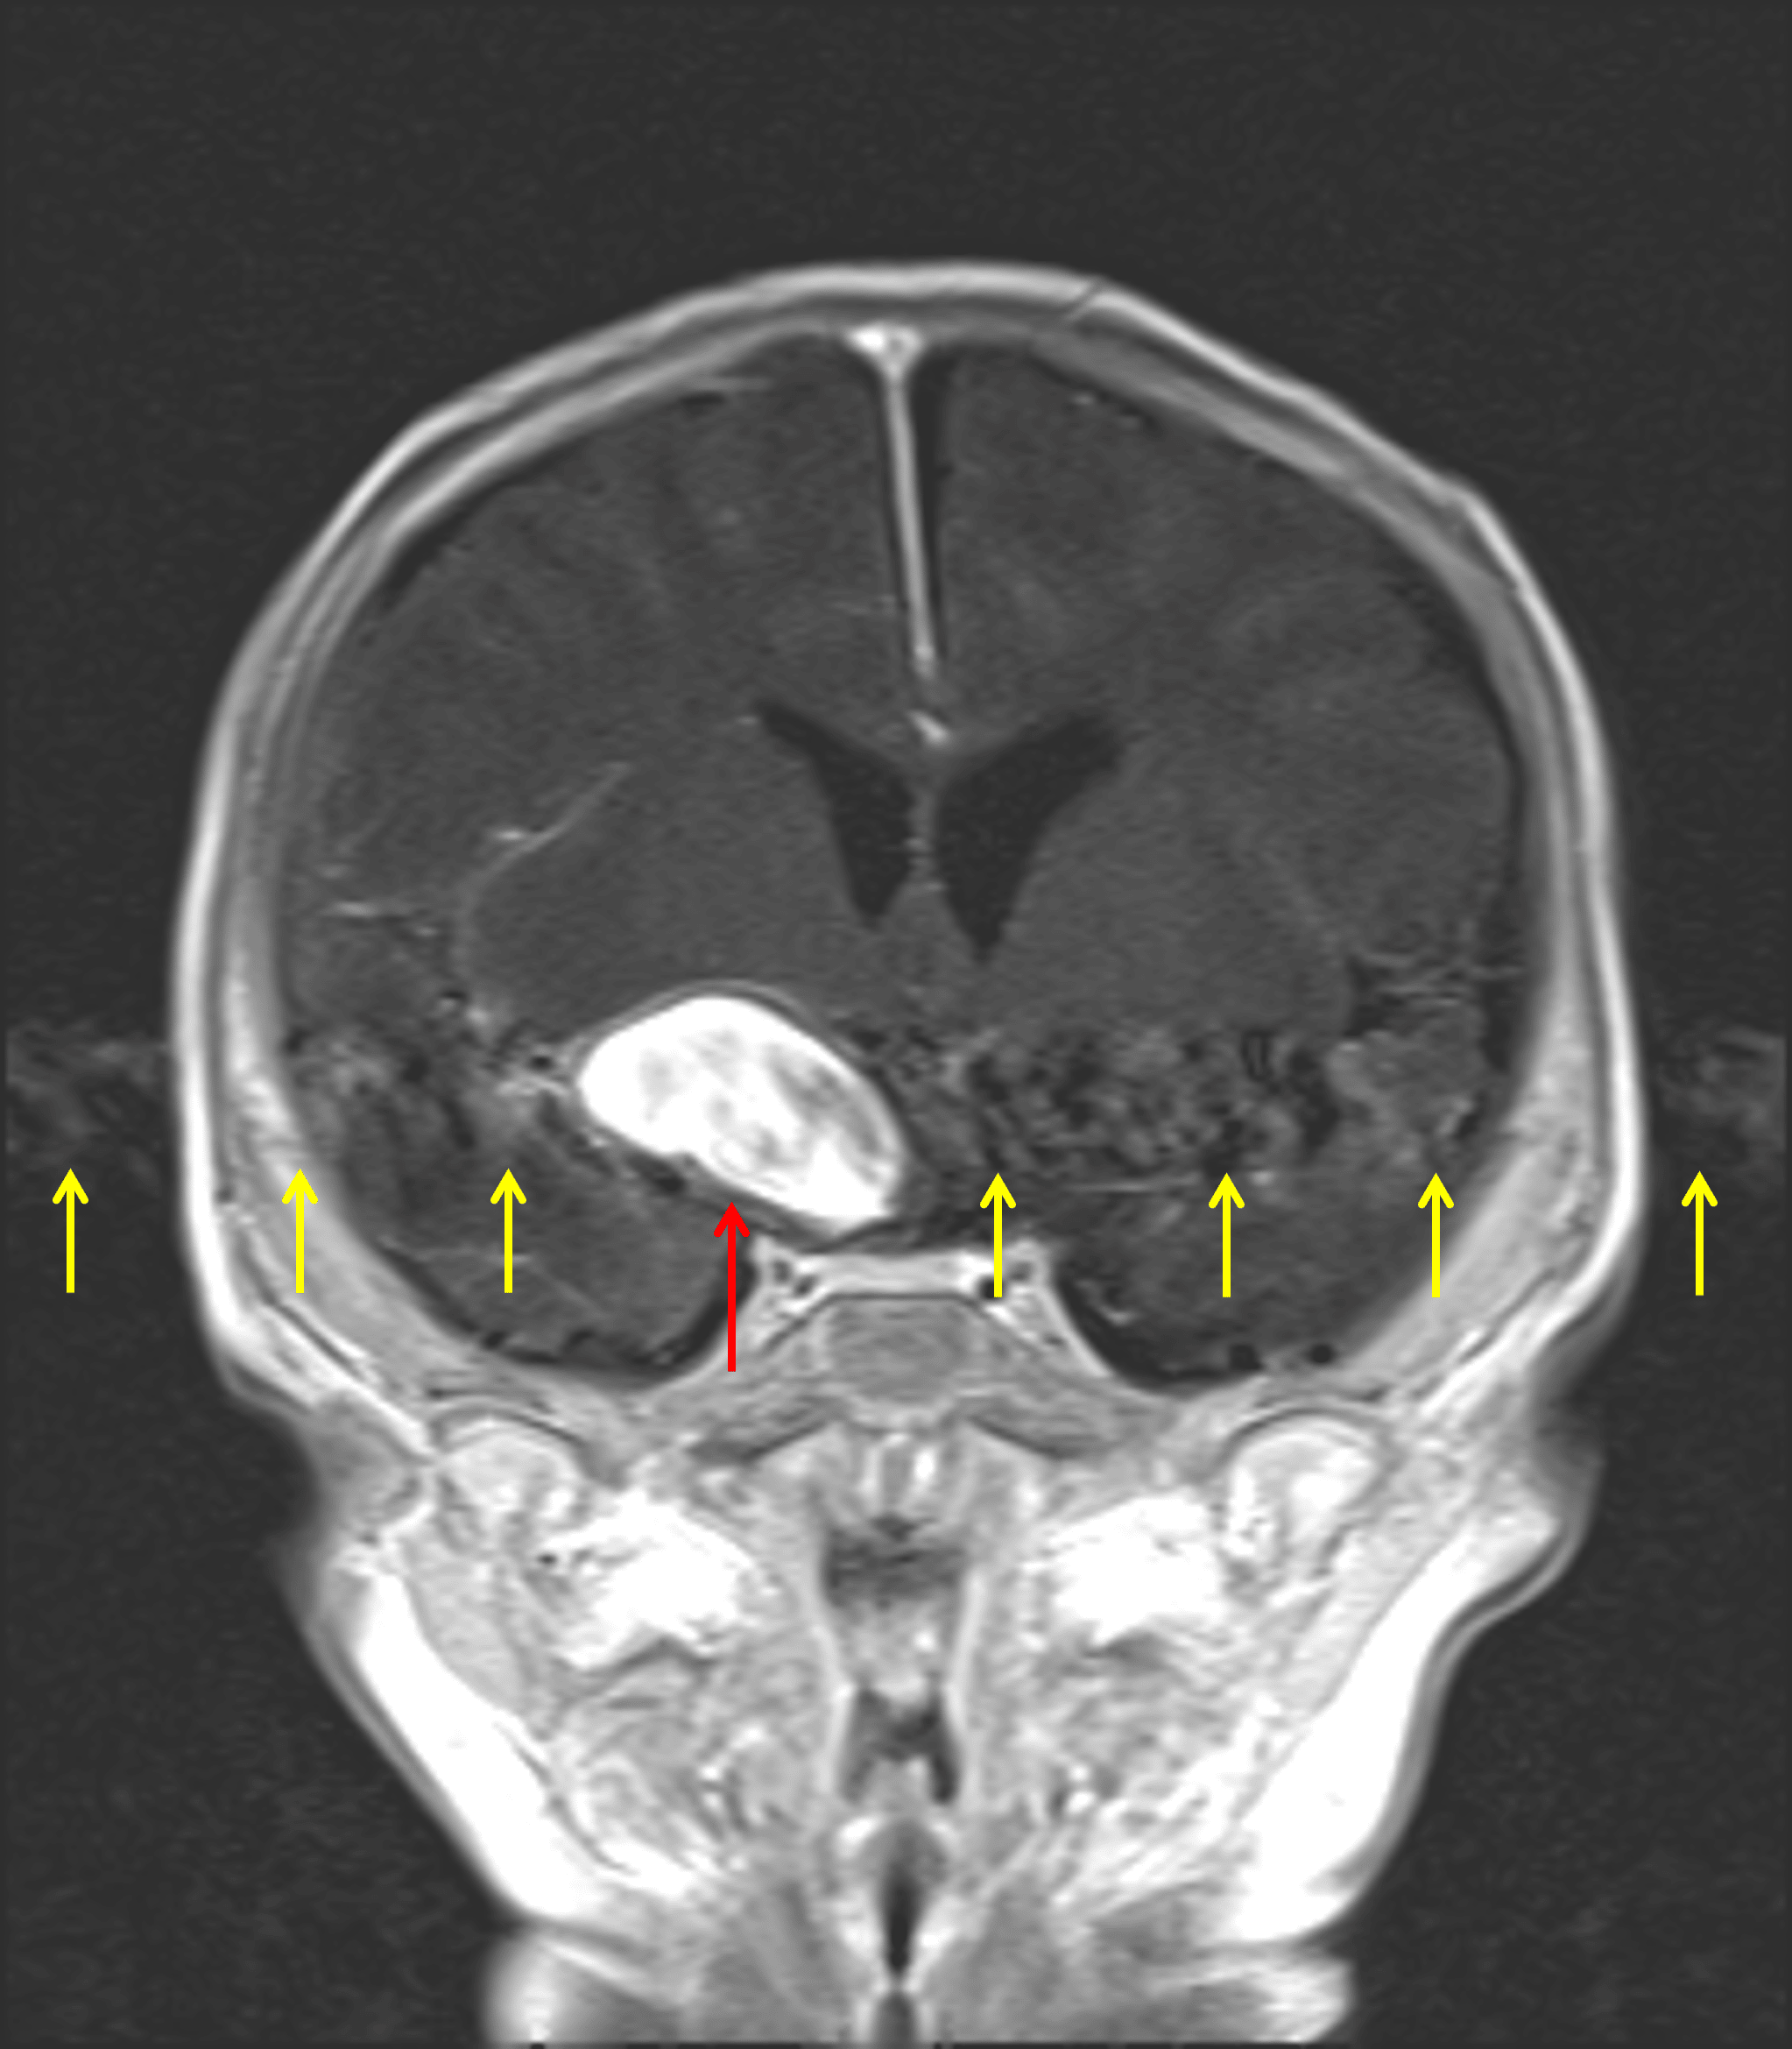

MRI

- Radiating pulsation artifact

- A more posterior fusiform component measuring up to 0.6 cm in thickness appears to supply right M2 branches, which remain patent

Diffuse internal enhancement on postcontrast imaging (red arrow) with corresponding radiating pulsation artifact (yellow arrows).